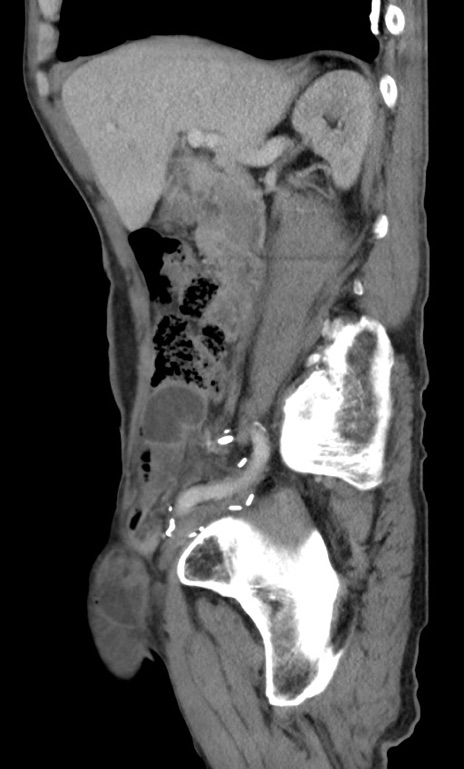

症例3(矢状断像)

【症例】 70歳代男性

【主訴】右鼠径部腫瘤、疼痛

【現病歴】本日朝より上記主訴あり、受診。

【既往歴】膀胱癌にて膀胱全摘、両側尿管皮膚瘻

【データ】WBC 5600、CRP 0.56